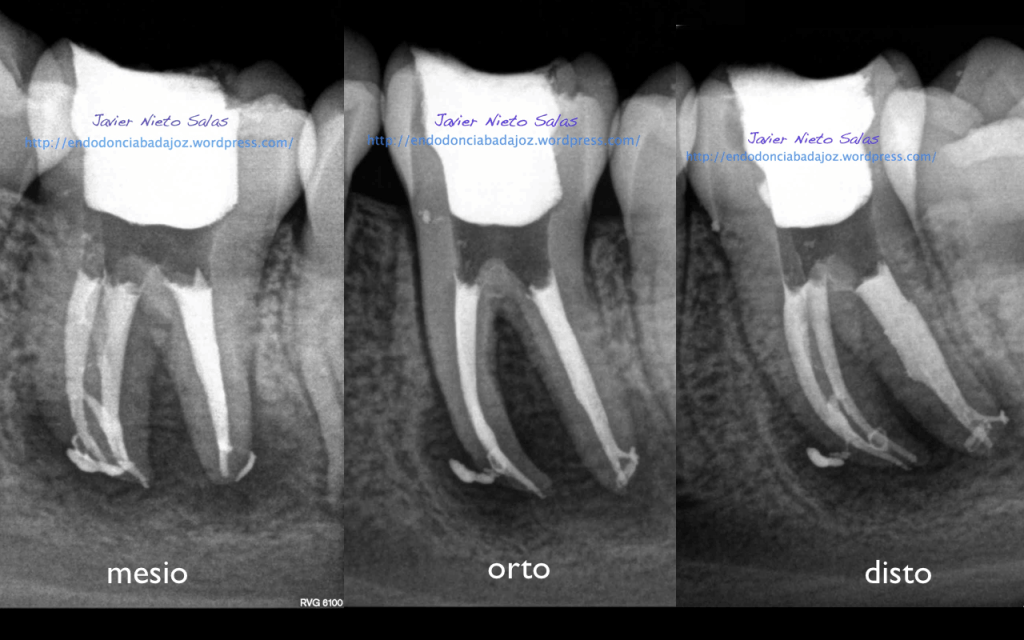

Se trata de un par de molares inferiores con lesiones apicales (Periodontitis apicales crónicas ). Consecuencia de caries profundas en su momento.

Se tratan del caso A y el caso B, por orden de posición, ambos casos se instrumentaron de la misma manera, elegimos Protaper hasta una F2, ambos casos se realizaron en una sesión tras abundante irrigación y finalmente se obturaron con condensación Vertical con la técnica de Ola continua de Buchanan complementando en el backfilling con guatpercha inyectada con la Pistola Obtura II.

Caso B:

También se llamo a revisión a los 10 meses.

Con respecto a tu pregunta sobre las dos últimas Rx, que son la revisión de las anteriores, de una periodontitis apical crónica de un 4.6, si puedes observar en la radiografía distalizada final, existe un istmo entre ambos conductos, y puede ser que exista un conducto lateral, pero como ya sabemos, existe una gran complejidad anatómica del sistema de conductos. El blog de Ronal Ordinola, es fantástico, y puedes ver esas anatomías en las que piensas en que la endodoncia es un verdadero RETO.